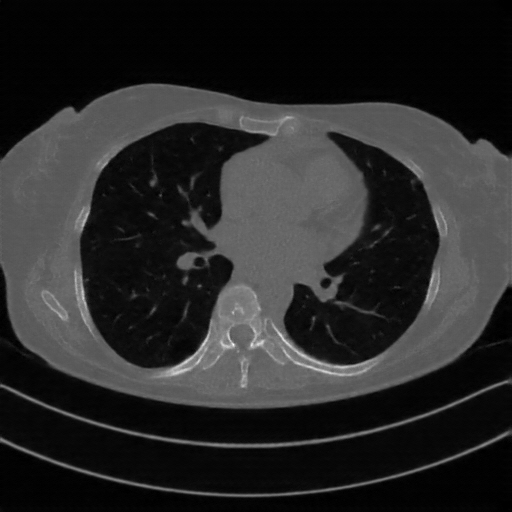

Generated VENOUS CT scan (A→B translation)

Lung window (WL -600, WW 1500 β†’ Low βˆ’1350, High +150)

Actual HU range: [-1241.2, 150.0]